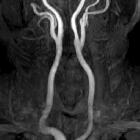

Ectopic

internal carotid artery presenting as an oropharyngeal mass. Magnetic Resolution Angiography after gadolinium administration shows the helicoids-ectopic course of the right ICA, immediately after the carotid bulb. Notice also, the significant stenosis of the controlateral left ICA.